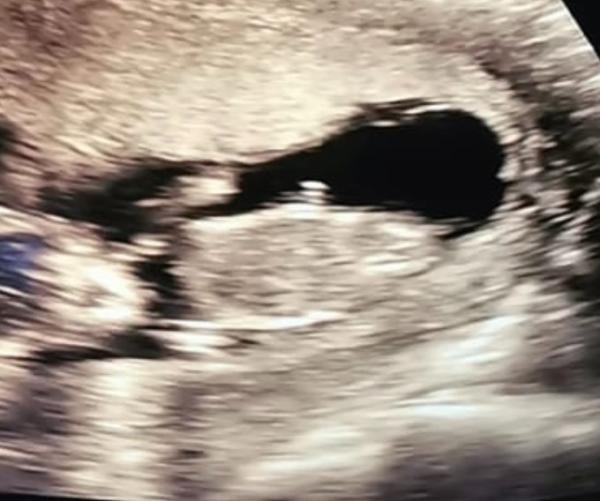

Alles war super Leider gab es kein outing ich muss mich jetzt bis Februar gedulden ...ich tippe auf Mädchen zu 60 Prozent ...

Bild zu Ultraschall - Forum für Juni - Mamis